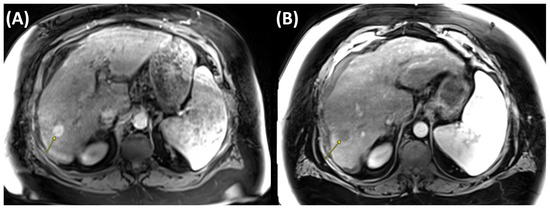

Case Report

Highlighting the Importance of Signaling Pathways and Immunohistochemistry Features in HCC: A Case Report and Literature Review

by Madalin Alexandru Hasan, Ioana Larisa Paul, Simona Cavalu, Ovidiu Laurean Pop, Lorena Paduraru, Ioan Magyar and Mihaela Doina Chirila

Reports 2025, 8(4), 197; https://doi.org/10.3390/reports8040197 - 3 Oct 2025

Background and Clinical Significance: In hepatocellular carcinoma (HCC), numerous signaling pathways become aberrantly regulated, resulting in sustained cellular proliferation and enhanced metastatic potential. Tumors that lack PYGO2 may not show the same types of tissue remodeling or regenerative features driven by the Wnt/β-catenin [...] Read more.

Background and Clinical Significance: In hepatocellular carcinoma (HCC), numerous signaling pathways become aberrantly regulated, resulting in sustained cellular proliferation and enhanced metastatic potential. Tumors that lack PYGO2 may not show the same types of tissue remodeling or regenerative features driven by the Wnt/β-catenin pathway, which could make the tumor behave differently from others that are Wnt-positive. PIK3CA-positive tumors are often associated with worse prognosis due to the aggressive nature of the PI3K/AKT pathway activation. This is linked to higher chances of metastasis, recurrence, and resistance to therapies that do not target this pathway. Case presentation: In this paper we present a rare case of hepatocellular carcinoma with PIK3CA-positive and PYGO2-negative signaling pathways, several key aspects of the tumor’s behavior, prognosis, and treatment options. Although alpha-fetoprotein (AFP) levels were significantly elevated, the CT and MRI examination showed characteristics of malignancy, HCC with secondary hepatic lesions and associated perfusion disturbances. The case particularities and immunohistochemistry features are highlighted in the context of literature review, the PIK3CA mutation suggesting the activation of the PI3K/AKT/mTOR pathway, a critical signaling pathway involved in cell survival, proliferation, and metabolism. Conclusions: Due to the aggressive nature of PIK3CA mutations, close monitoring and consideration of immunotherapy and targeted treatments are of crucial importance. Full article